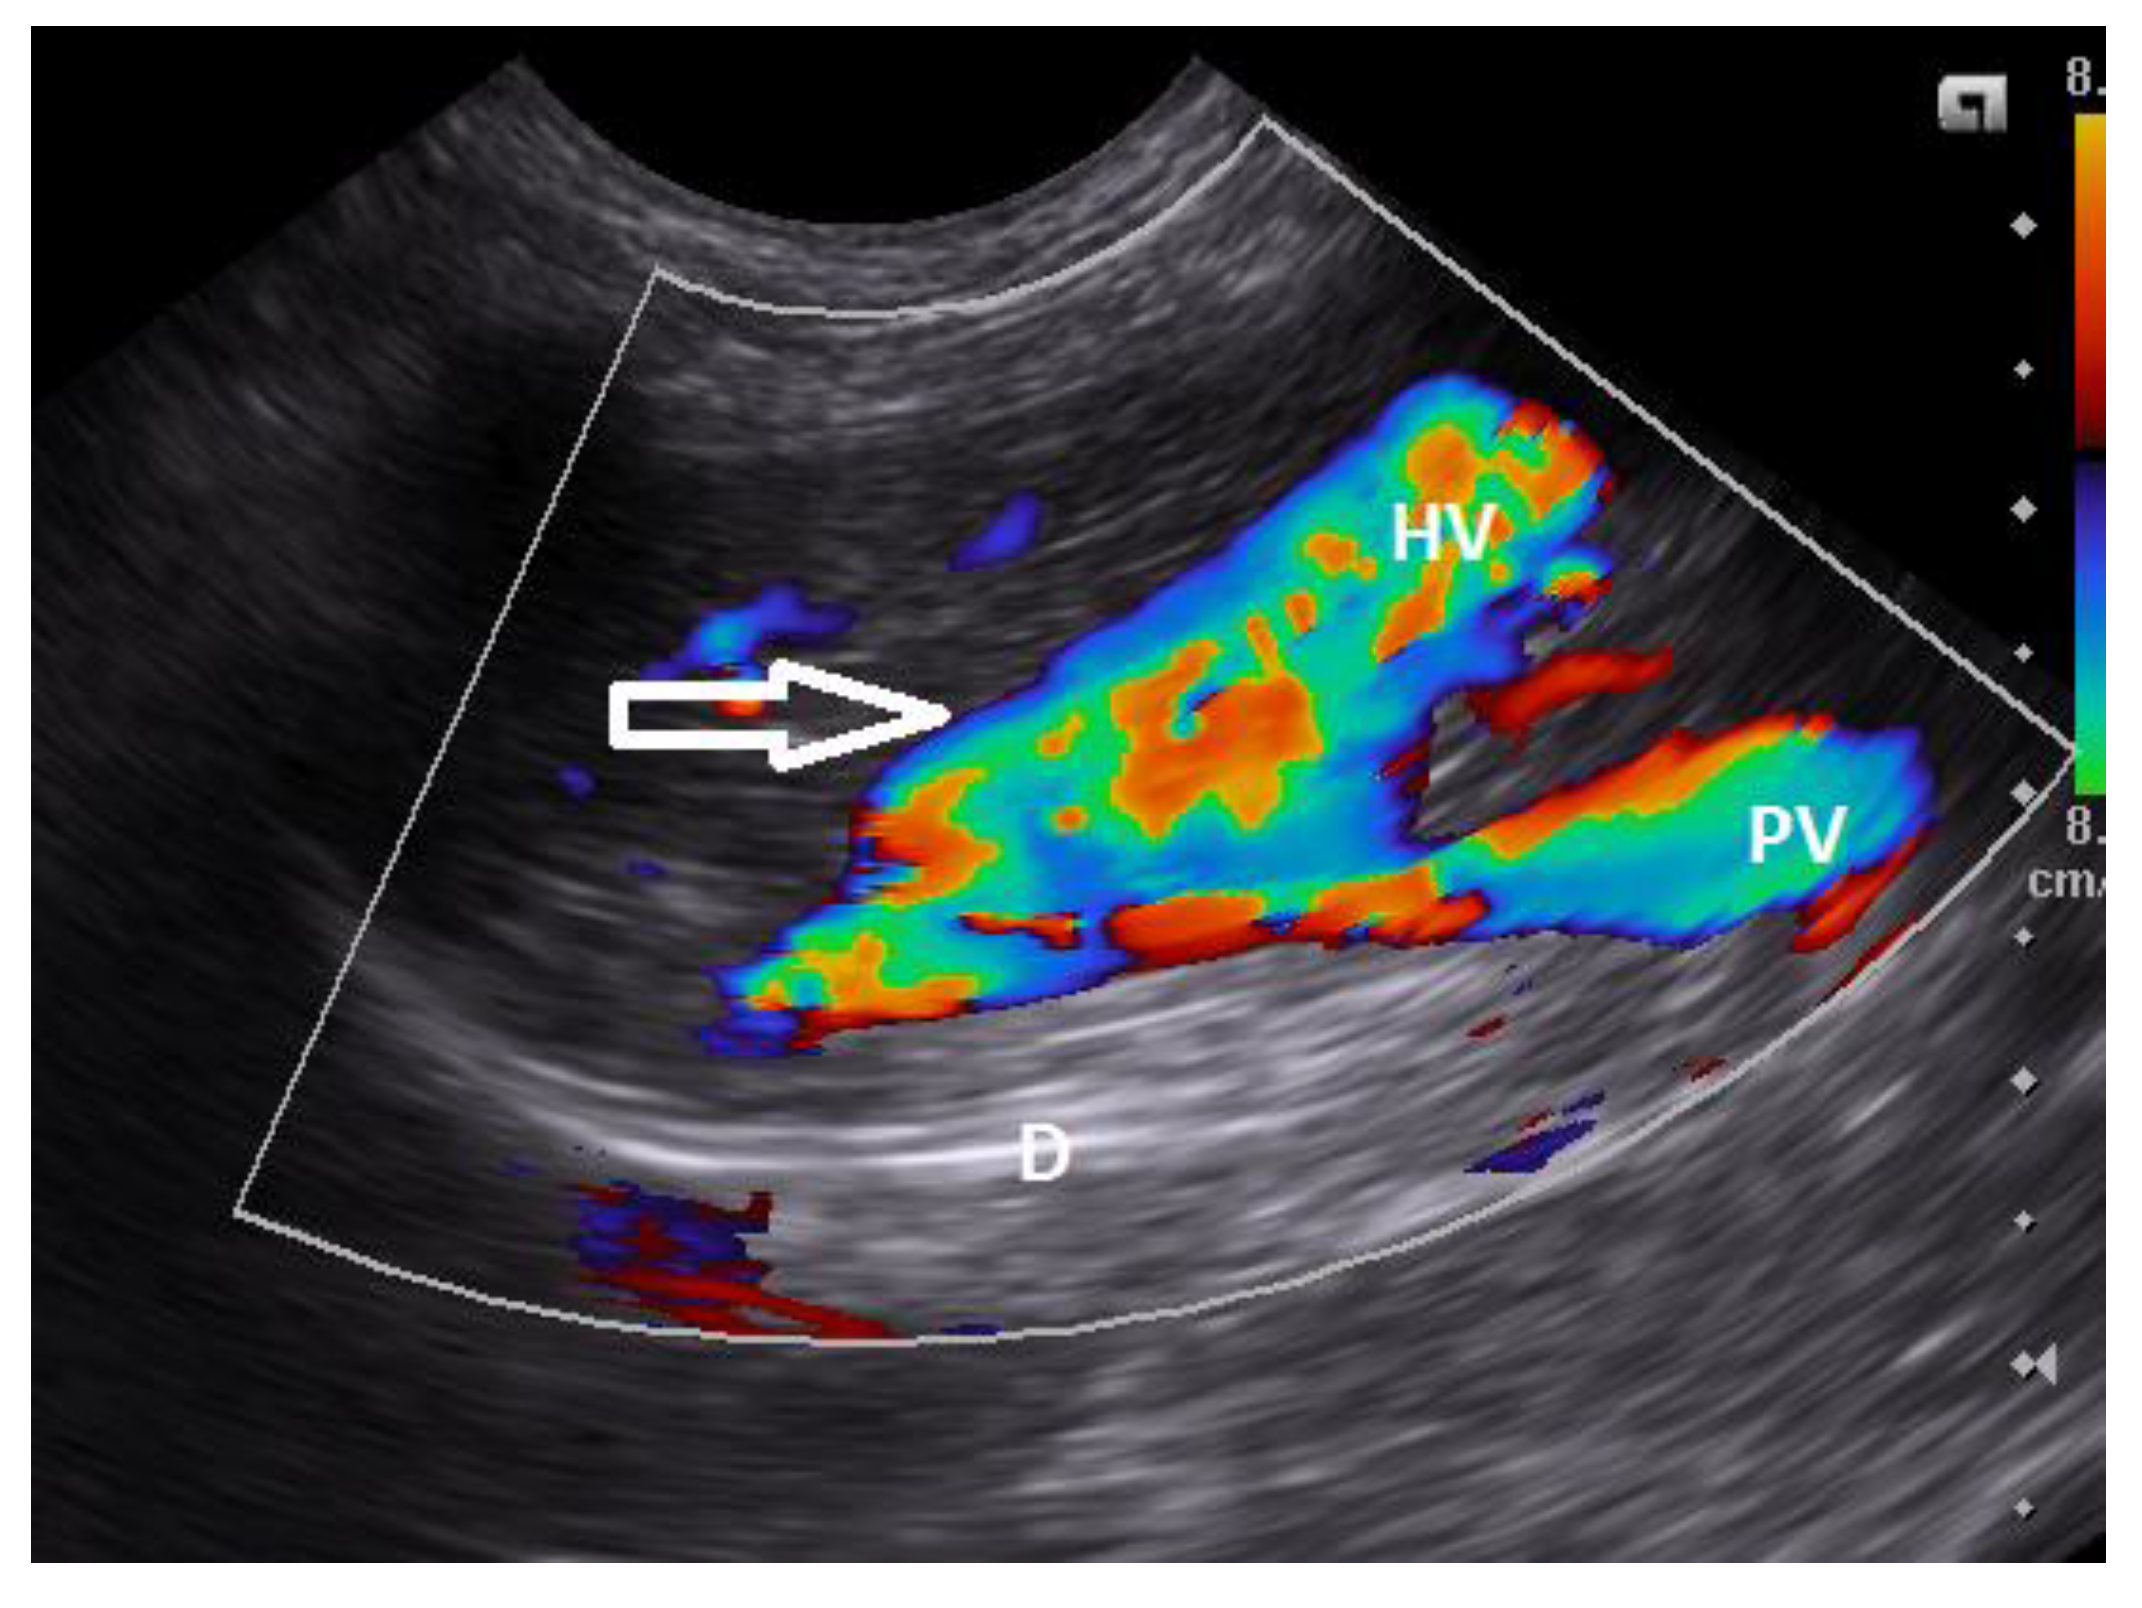

6. Clinical Signs/Physical Examination

9. Diagnostic Imaging